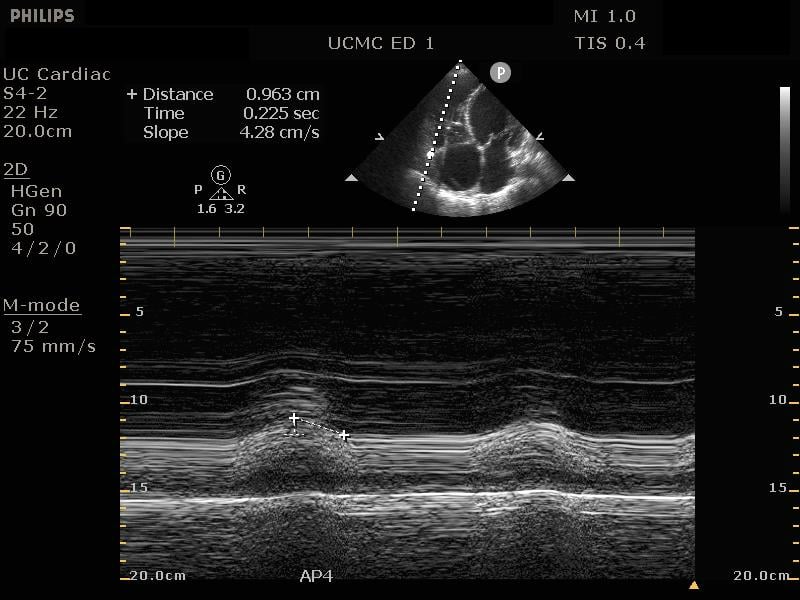

The cardiac component is essential to evaluation of a hypotensive patient as it can provide valuable information about cardiac physiology and etiology of shock. The goal of the cardiac portion of the examination is to classify presence or absence of pericardial effusion, pericardial tamponade, evaluate left and right ventricular contractility and chamber size and thus link these findings to the etiology of shock. Pericardial effusion with tamponade may be identified as a cause of obstructive shock. As fluid and pressure in the pericardial sac increases, early diastolic collapse of the right ventricular free wall is seen. (Video 1) This can be assessed visually in the parasternal long view by placing an M-mode line through the right ventricle (RV) and left ventricle (LV), including the interventricular septum and anterior leaflet of the mitral valve. (Figure 3) This allows for easy identification of right ventricular diastolic collapse, which is indicative of tamponade physiology.

Figure 3. Right ventricular diastolic collapse viewed in M-mode. Note motion of mitral valve leaflet, in the mid-field. Valve opening indicates diastole, which can then be compared to the collapse of the right ventricle in the near field.